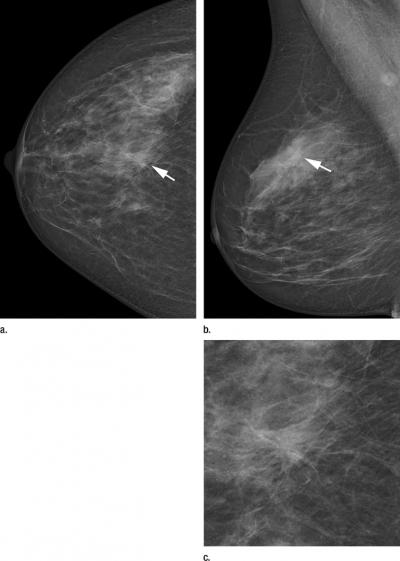

For the study, Dr. Heindel and colleagues analyzed data from the mammography screening program in North Rhine-Westphalia, the most populous state in Germany. They compared the screening performance of a DR photon-counting scan system with those of statewide operating screening units using different digital technologies. During the study period (2009 – 2010), 13,312 women were examined using the photon-counting system, and 993,822 women were screened with either CR or DR systems alone.

In addition, the mean average glandular radiation dose of the DR photon-counting scan system was significantly lower than the conventional DR systems with the individually used parameters of the automatic exposure control.

The photon-counting technique also offers lateral dose modulation during the image acquisition, which can help account for differences in breast density. Cancer often is more difficult to detect in women with dense breasts.

"The innovative photon-counting technique offers further research potential," Dr. Heindel said. "One future research direction is the application of spectral imaging for quantification of breast glandular tissue, addressing the problem of breast density."